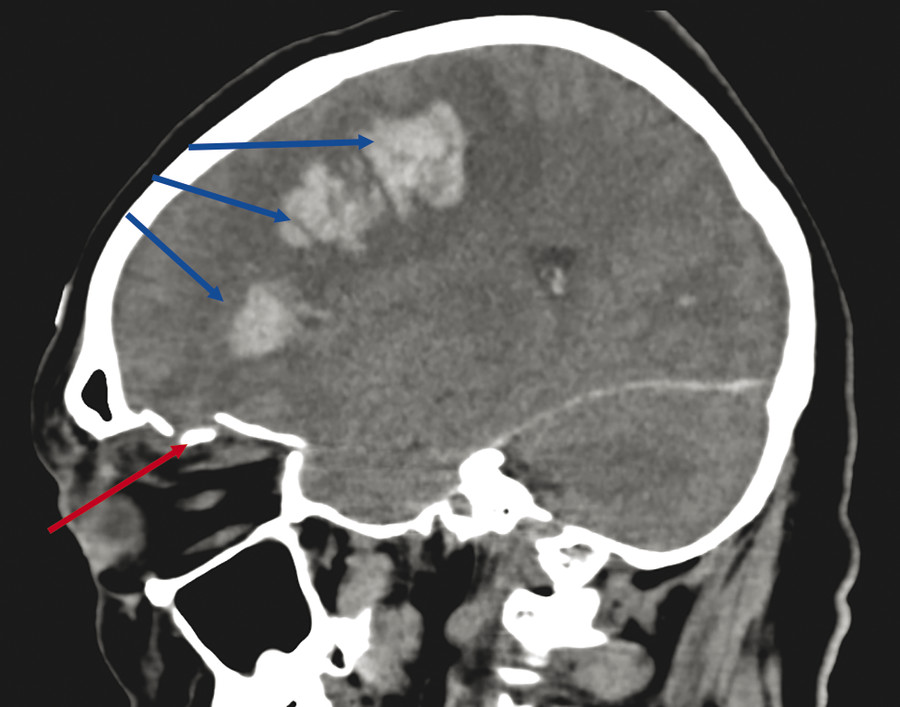

Examine and treat the patient for all injuries (Fig. 25‑1 and Fig. 25‑2).

The examination of patients who have sustained eyelid and/or orbital trauma should be performed very delicately and meticulously to exclude associated trauma to the globe (Fig. 25‑1).

Lacerations of the eyelid have an underlying perforating injury of the globe, or even a penetrating injury of the brain, until proven otherwise (Fig. 25‑2).

Resuscitation, if needed, and stabilization of vital signs are the initial goals for the treatment of any trauma patient. It must be borne in mind that any patient who has sustained trauma has the potential to develop shock during the evaluation process as a result of occult serious or life-threatening injury. Periodic monitoring of vital signs during the examination process is therefore mandatory. Once the patient has been stabilized, the presence of life-threatening associated injury must be ruled out. Understanding the mechanism of injury is most helpful in this regard (e.g., an eyelid injury from a screwdriver in a child or a fall onto a bamboo cane in the garden in an older individual may be associated with a serious central nervous system [CNS] injury [see Fig. 25‑2]).

All patients with significant eyelid trauma should receive a complete ophthalmic examination, but the order and venue for the examination (in the emergency department or the operating room) are dictated by the severity of associated ocular injury. It is important to ensure that all steps have been taken to exclude possible associated trauma (e.g., CNS injury in a patient with an upper lid puncture wound) by CT before the patient is anesthetized. It is highly unsatisfactory to discover other injuries that require the expertise of other specialists or operating facilities that are located elsewhere once the patient has been anesthetized.